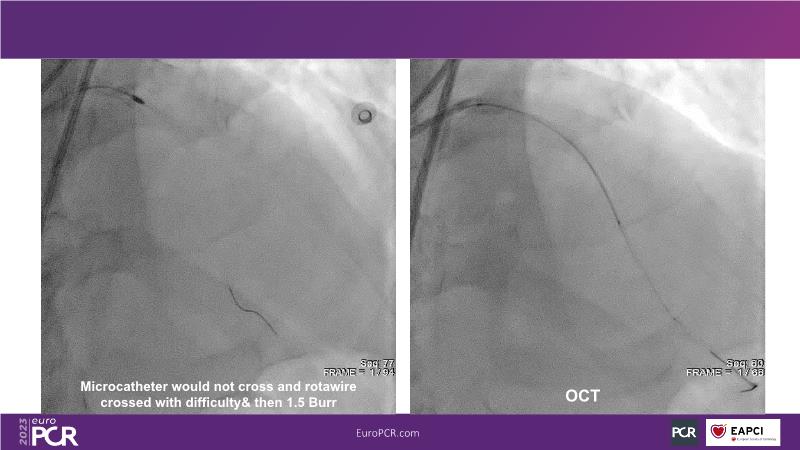

In this session, review the evolution in the use of IVL over the last few years, with a widening of the indications, observe that OCT can underestimate the number and depth of calcium fractured induced by IVL, or see that the technique is safe and effective in high-risk patients, including ACS patients, as demonstrated in real-world registries, among others!

- To understand how intravascular lithotripsy (IVL) in clinical practice has evolved over the last five years

- To evaluate the effects of IVL in different patterns of calcific coronary disease